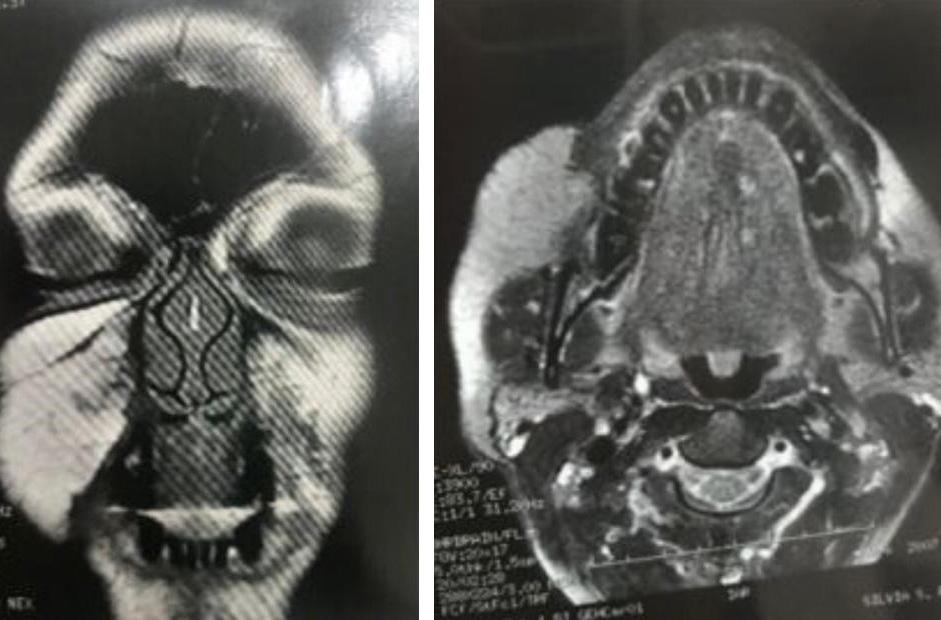

Tratamento da síndrome de Parry-Romberg e da esclerodermia linear em golpe de sabre, com aplicação do ácido

76 poli-L-láctico (PLLA): avaliação da resposta clínica e ultrassonográfica de alta resolução

Renato Roberto Liberato Rostey, Cristiane Ferreira Rallo de Almeida, Danilo Olavarria D’Aquino, Caio Leal Carvalho